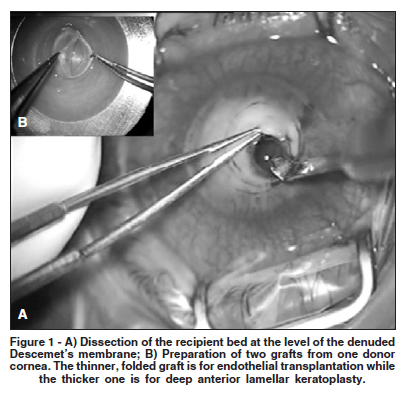

A 60-year-old woman was referred to us, after her painless left eye, with a history of recurrent herpes simplex keratitis, had been treated with 1% prednisolone drops for ten days. Visual acuity (VA) was light projection. The central 8 mm corneal portion was opaque, edematous, partially necrotic, and anesthetic, with a paracentral, 4x3 mm melt down to Descemet's membrane. Her right eye was inconspicuous. The recipient bed was prepared by a central, 7.0 mm, partial thickness corneal trephination and dissection at the level of DM partially denuded by melting (Figure 1A). The dissected stroma was cut off along the trephination mark, and the intact, clear DM was ready to be covered with a lamellar graft.

A whole globe of a 43-year-old donor was used for a manual preparation of two 8.0 mm corneal grafts: one, intended for DSEK, which included endothelium together with Descemet's membrane and a thin layer of the posterior stroma; and the other, which included most of the donor stroma together with epithelium, for the DALK procedure (Figure 1B). A 5.0 mm vertical cut with a rounded blade and a stop at 0.5 mm (BD Pharmaceuticals) was made at the limbus using some pressure to penetrate as close to DM as possible and the initial stromal cleavage was made with a Paufique knife (Geuder, Heidelberg, Germany), followed by a lamellar dissection from limbus to limbus with a Castroviejo spatula (Geuder, Heidelberg, Germany). After the corneoscleral button had been excised, an 8.0 mm trephine was used to cut it from the endothelial side. The endothelium was covered with a drop of Amvisc (Bausch and Lomb Pharmaceutical, Berlin, Germany). The grafts were divided, and the thicker graft was put onto the recipient bed, (Figure 2A) and sutured; 0.5% prednisolone eye drops were given t.i.d. for three months and once daily for another three months. Oral acyclovir at 400 mg five times daily was given for three months, followed by twice daily for another 12 weeks. Ciliary hyperemia was minimal. Neither the aqueous flare nor corneal inflamation were observed.